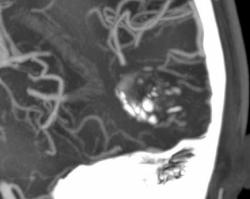

Еще одна сосудистая мальформация - кавернозная ангиома или кавернома. Раньше относили к опухолям.

Видна группа сосудистых лакун неправильной формы, кальцинаты. Перифокальных изменений нет.

Больному также проводили МРТ (снимков у меня нет), которая очень хорошо выявляет каверномы.